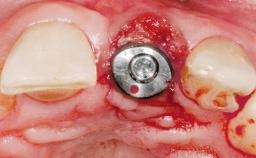

Immediate Placement of an Implant in a Maxillary Right Central Incisor Site

A 30-year-old female patient was referred to the office for the treatment of tooth 11. Her chief concern at the initial visit was to inquire, “Why is my tooth pink?” Upon clinical examination, it was determined that tooth 11 had a previous history of trauma and that the clinical crown had become noticeably pink in color as a result of internal resorption. This diagnosis was confirmed radiographically, indicating a large radiolucency involving the central and distal portions of the clinical crown. It was determined that restoration of this tooth was not possible, and that extraction was indicated. The presence of a mid-line diastema, which the patient wanted to reproduce, directed the treatment plan for tooth replacement utilizing a dental implant.

| Placement Protocol | Immediate implant placement |

| Tooth Site | Maxillary incisor or canine |

| Socket Morphology | Single-root socket |

| Socket Integrity | Sufficient, with intact bone walls |